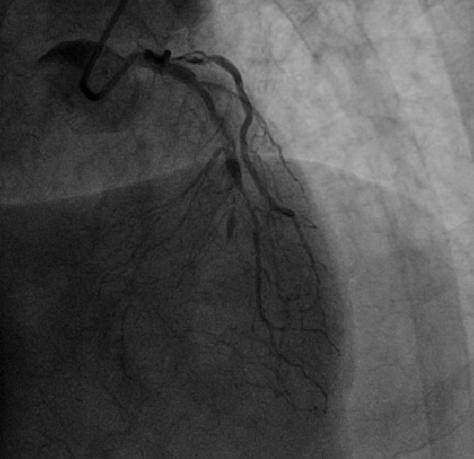

病例一

患者为60岁的老年男性,因反复的心绞痛在当地医院进行治疗,冠状动脉造影发现左前降支中段闭塞并伴有严重钙化,当地医院进行反复尝试,虽然导丝可通过闭塞病变到达远端,但是因钙化严重球囊无法通过,无法进一步治疗。

为解决问题,患者辗转于多家医院,均告知很难开通,必须搭桥。之后患者慕名找到刘巍主任。刘巍主任阅片后发现,病变不仅在前降支中段,对角支也有严重狭窄,考虑如果使用旋磨并不能保护对角支血流,所以决定使用准分子激光技术消融斑块开通血管。手术过程非常艰难,由于前降支血管闭塞,之前外院的医生已经对血管进行扩张处理,所以导丝很容易进入到血管夹层中,反复尝试才将导丝经过真腔送至血管远端。使用球囊扩张后,计划使用IVUS检查对前降支进行评估,但由于钙化严重IVUS无法通过,如果勉强植入支架,支架肯定膨胀不良,后果不堪设想。

刘巍主任团队应用0.9mmECLA激光导管多病变处反复进行高能量消蚀,松解钙化病变,之后成功植入支架,术后效果非常满意。

CAG显示LAD近中段闭塞

术后LAD显著改善